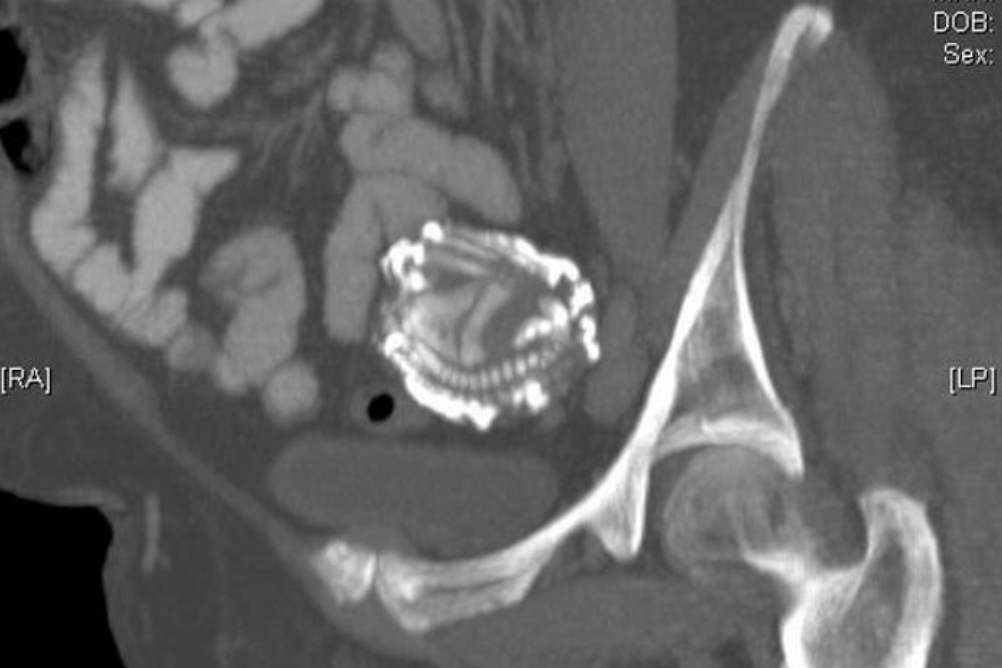

의료진은 종양을 의심해 초음파 검사로 배 안을 살펴봤는데 정체가 불분명한 거대 덩어리가 있는 것을 확인했다.

이에 정밀 검진을 진행했는데 그 결과 할머니 배 속에 있던 덩어리는 충격적이게도 ‘태아’로 확인됐다.

담당 의사 타이비 쿠아짜니(Taibi Ouazzani)는 “여성 환자가 첫 임신 당시 ‘자궁 외 임신’을 한 상태였다”라며 “수정란이 복강(배 안)에 착상됐었고, 이 때문에 지금까지 발견되지 않은 것”이라고 설명했다.